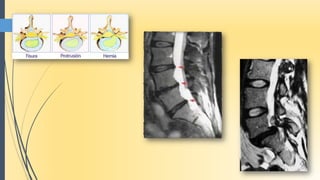

La columna

 Núcleo para movilizar

Ligamentos

Nocicepción (ligamentos = receptores +++)

 irritación de la capsula del disco